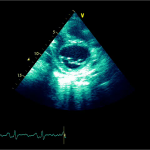

Ecocardiografia transtoracică

- Formaţiune hiperecogenă cu suprafaţa neregulată, care tapetează peretele liber al VD, grosime de 12 mm

- Dispusă de sub planul valvei tricuspide până in apropierea conului de ejecţie al valvei pulmonare

- SIV aplatizat

Ecografia transesofagiană:

Confirmă datele de la ecografia transtoracică